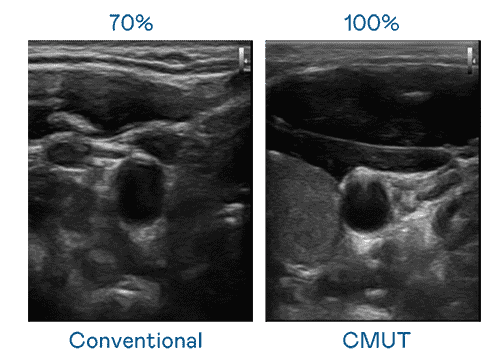

CMUT 技术是一种用电容式微机电元件来产生超音波讯号的技术。。与传统 PZT 压电式技术相比,,,CMUT 频宽增加 30%,,更宽频的超音波讯号让影像解析度大幅提升,,,,是实现高影像品质医疗超音波扫描、、促进精准医疗发展的关键技术。。。。

大频宽带来超清晰影像

超音波影像的解析度高低,,,,首先取决于探头能发出的讯号频宽。。NG大舞台 CMUT 可提供高清晰的超音波讯号,,,,提供高频宽、、、高灵敏度、、影像纹理细节更高的超音波影像,,协助医护人员缩短影像判读时间及利用精准的医疗影像进行诊断。。